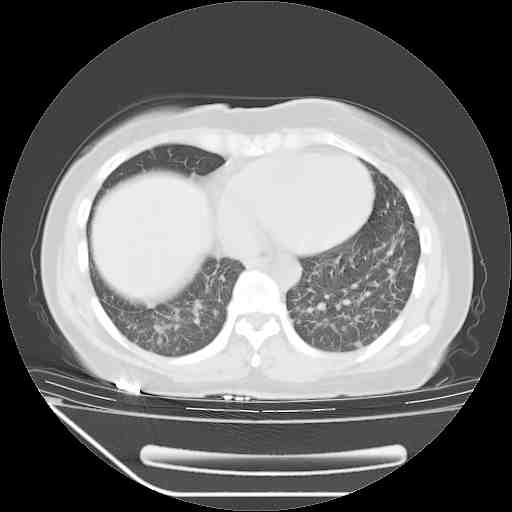

肺癌并肺内转移,这种疾病治疗后在影像上看略有好转,不是很显著,但是肿瘤治疗效果影像只是一方面。

标准的细支气管肺泡癌呀!治疗后病情有所控制,也没治愈的迹象!

应该是比较典型的细支气管炎,4个月的时间不说明问题;有时候疾病是有个相对稳定期的,如果喝10元一斤的茶叶估计也会这样。